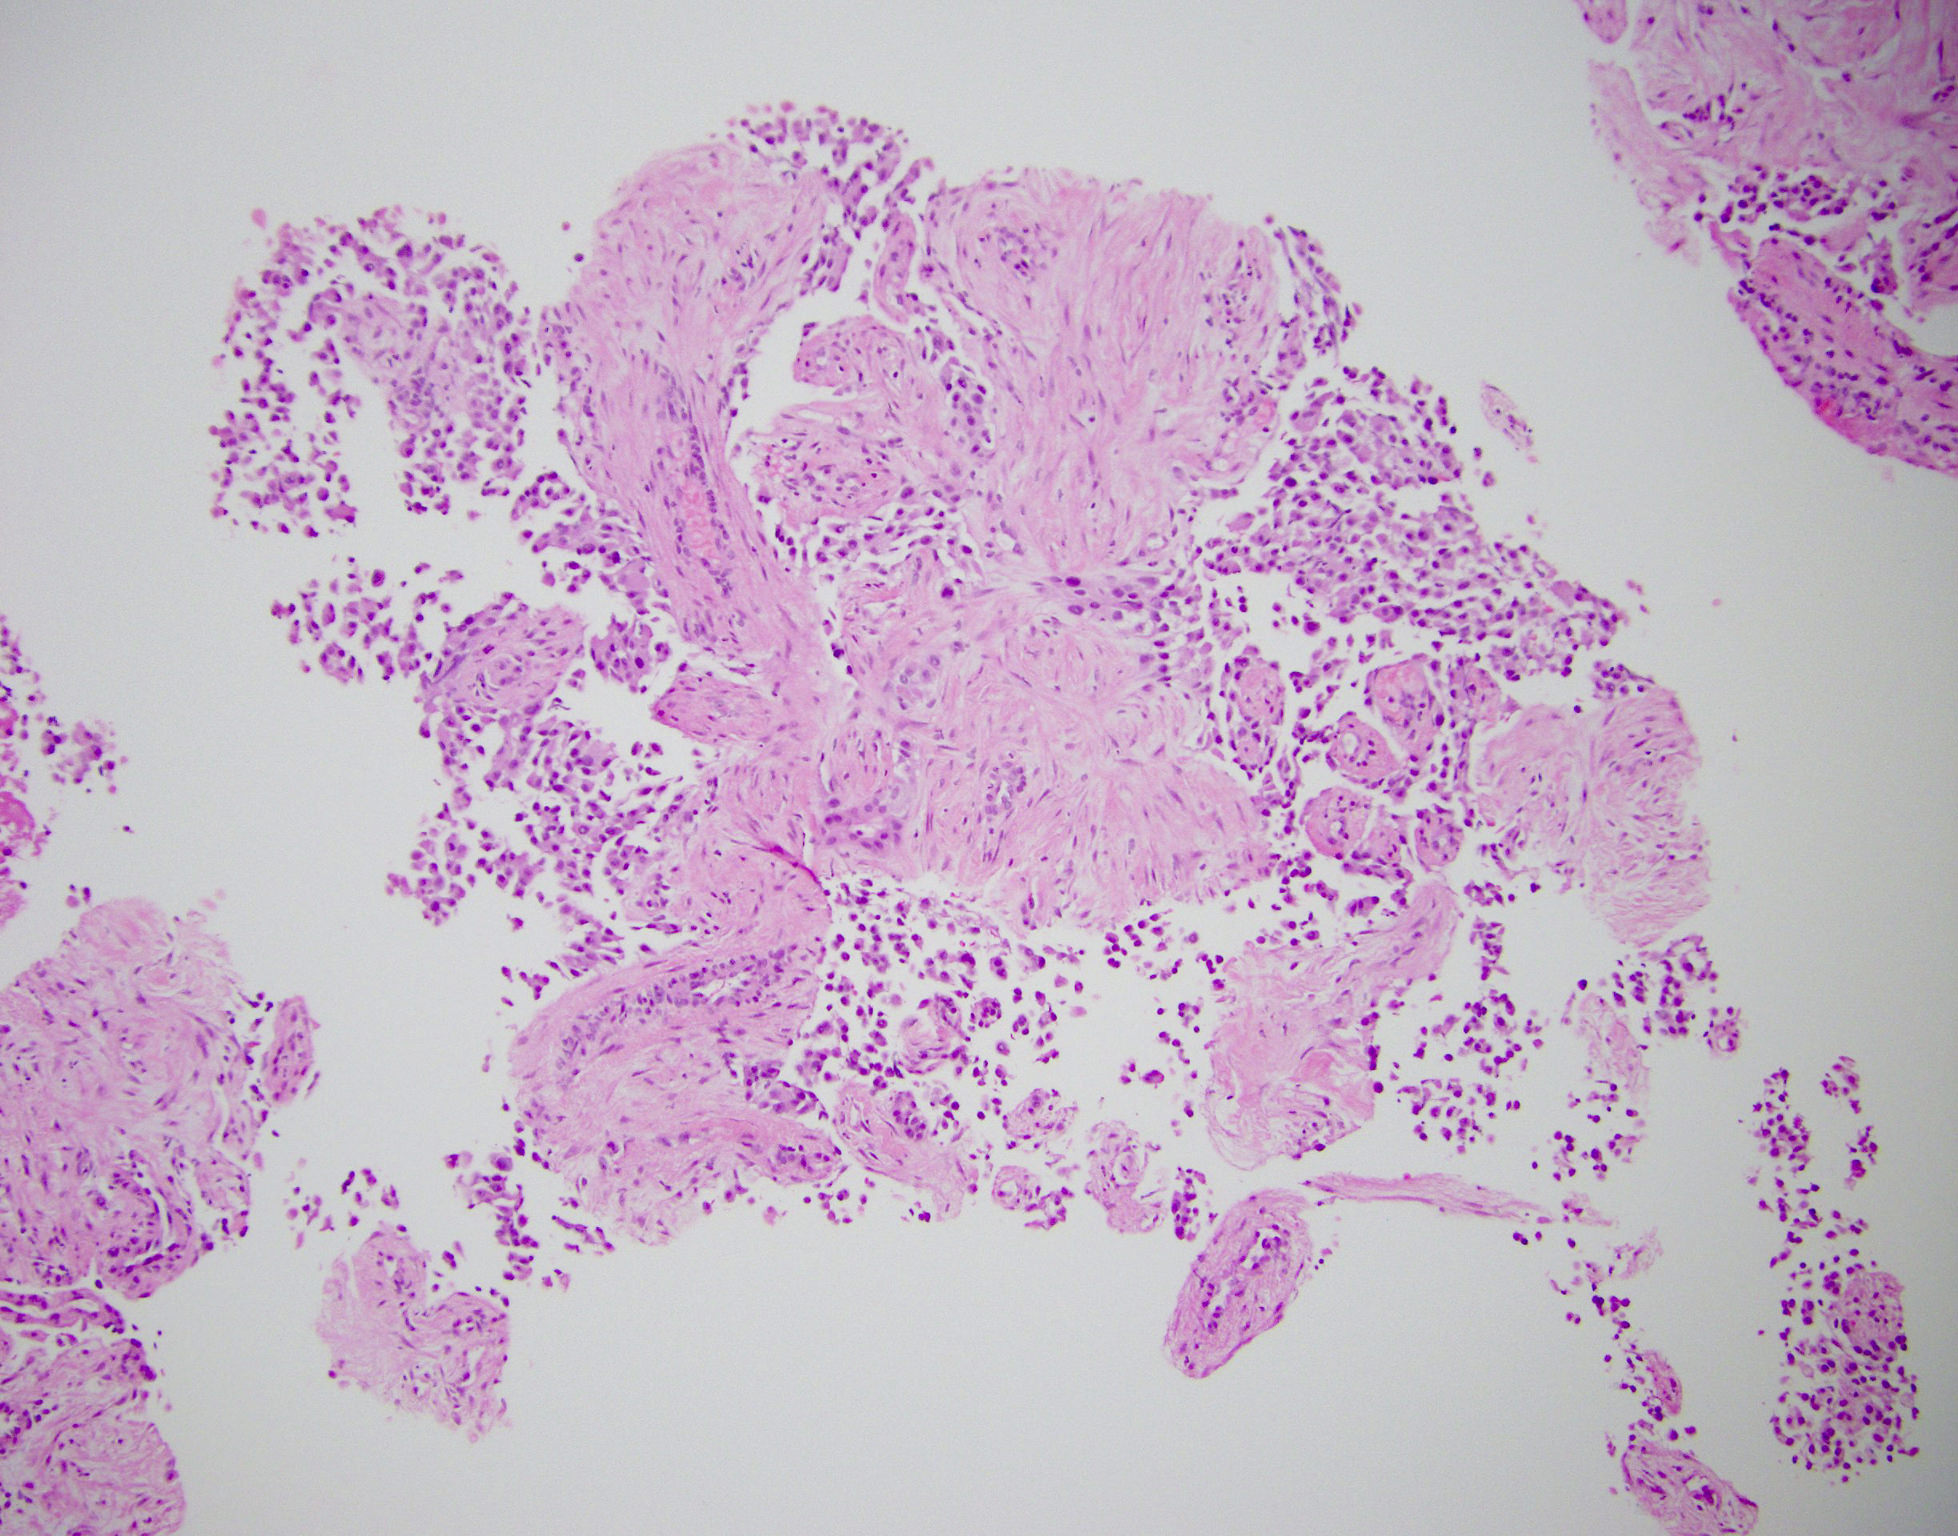

Microscopic (histologic) description

- Tumors are heterogeneous, with variable admixture of solid and pseudopapillary areas

- Solid areas are comprised of uniform cells admixed with capillary sized blood vessels

- Pseudopapillae are formed due to tumor cells getting detached from blood vessels forming fibrovascular stalks or rosette-like structures (Arch Pathol Lab Med 2020;144:829)

- Stroma usually shows various degrees of hyalinization or evidence of degeneration, such as hemorrhage, foamy macrophages, calcification and cholesterol clefts

- Tumor cells usually have a moderate amount of eosinophilic cytoplasm with intracytoplasmic hyaline globules (PAS+ and diastase resistant, positive for alpha-1-antitrypsin) and perinuclear vacuoles (Am J Surg Pathol 2011;35:981)

- Relatively uniform nuclei with finely textured chromatin, inconspicuous nucleoli and characteristic longitudinal grooves

- Variants include clear cell, oncocytic and pleomorphic

- Rare mitotic figures

Microscopic (histologic) images

Contributed by Monika Vyas, M.D., Omid Savari, M.D. and Raul S. Gonzalez, M.D.